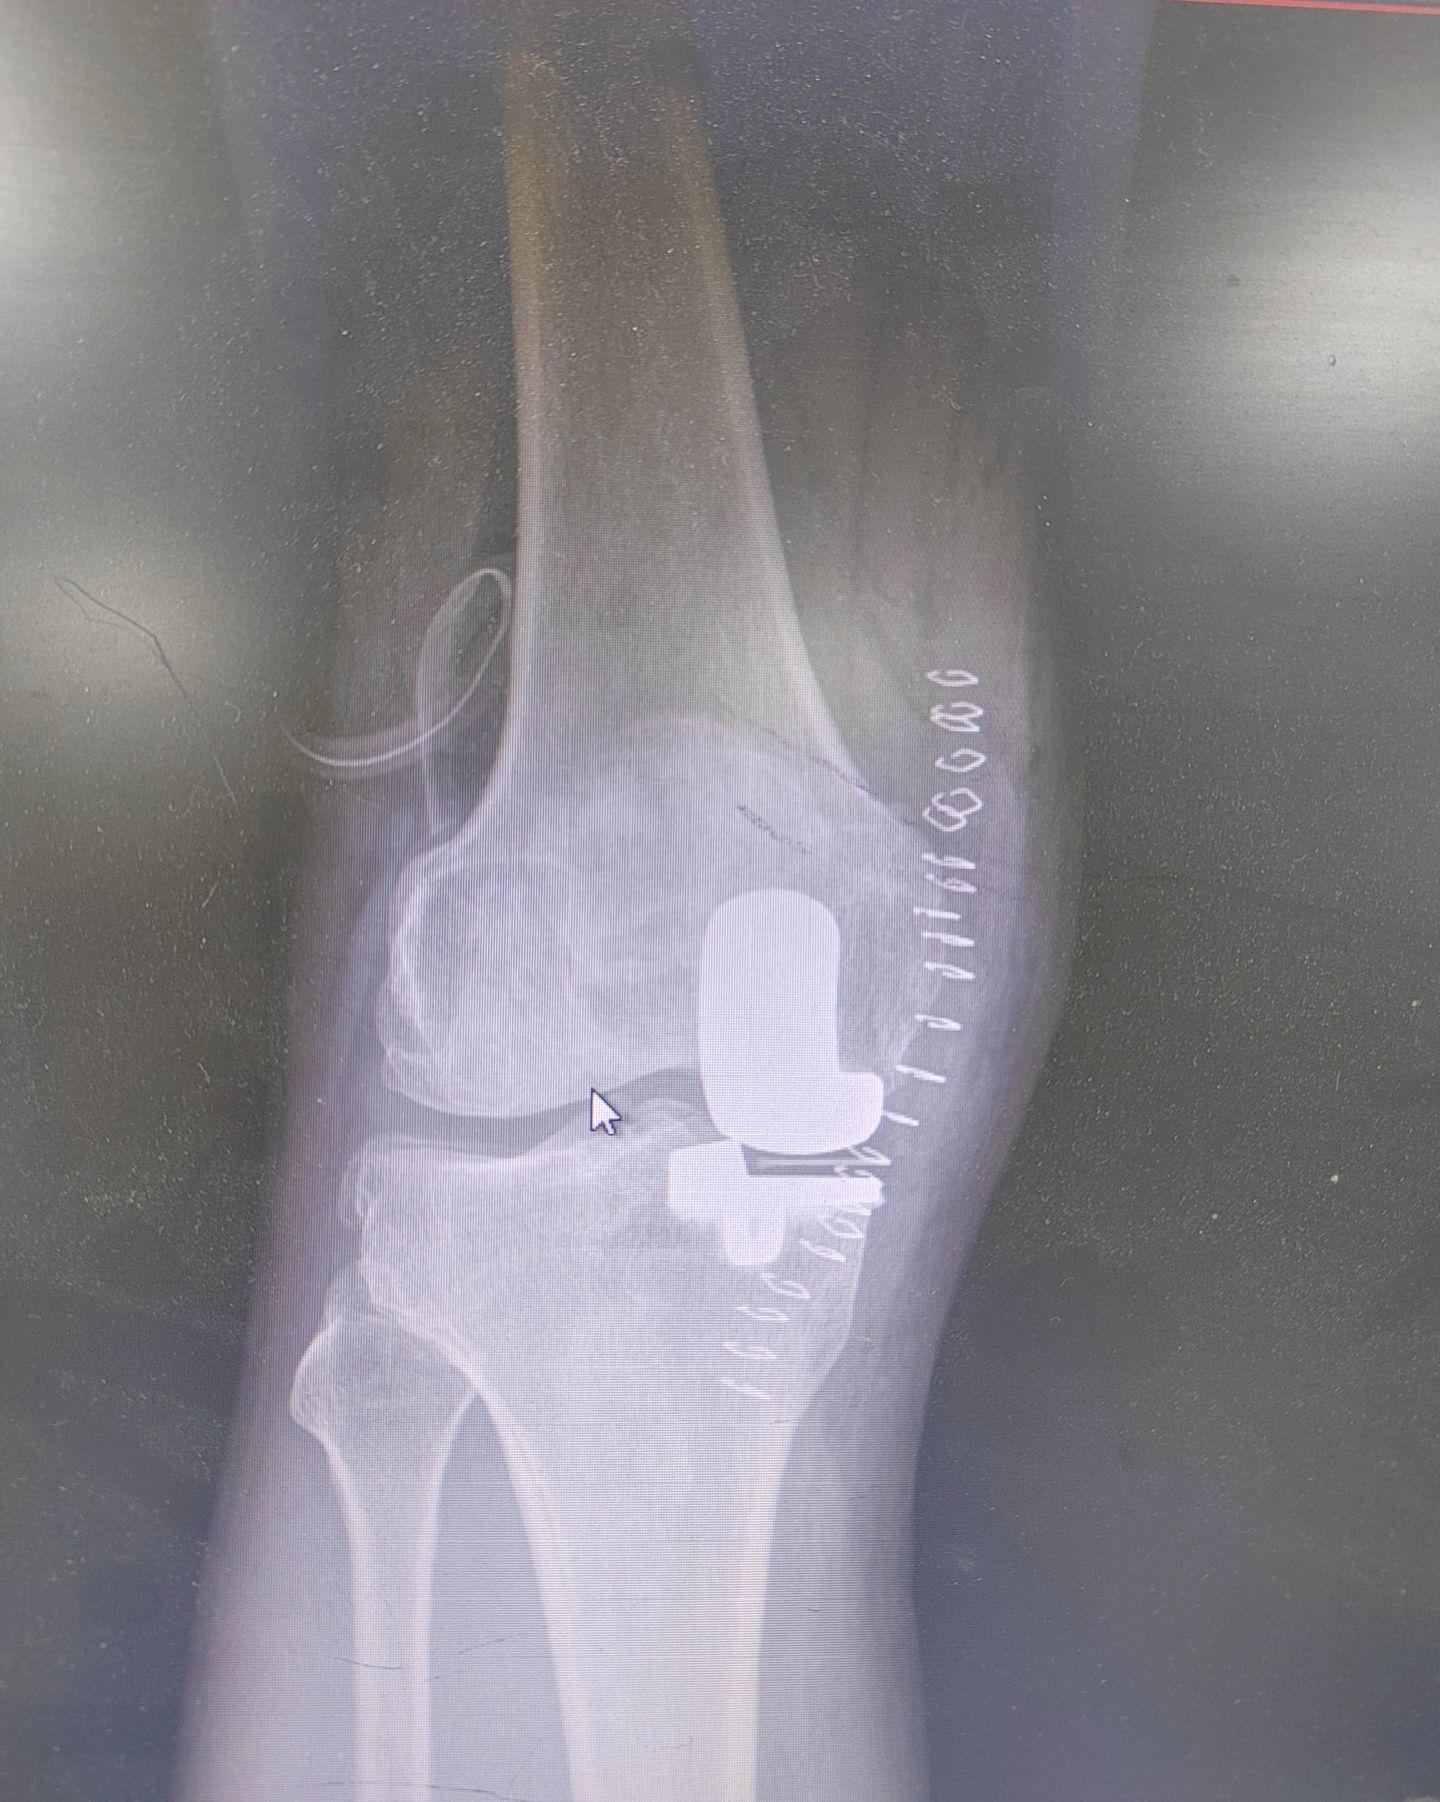

单髁置换术。(看图猜假体)每款假体都有自己的优点,不要单纯追求国产或进口,也不要单纯追求活动平台或固定平台,适合自己才是最好的。愿每一位病人都能快速顺利康复🌹